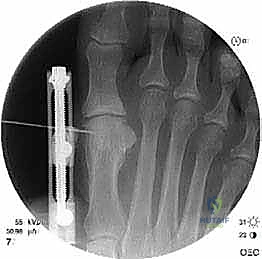

الخطوة الخامسة: التثبيت الداخلي القوي (Internal Fixation)

لضمان التئام العظم في وضعه الجديد والطويل، يجب تثبيته بقوة شديدة. يستخدم الدكتور هطيف أحدث الشرائح المعدنية التيتانيوم ذات الزاوية الثابتة (Locking Plates) والمسامير الدقيقة. هذا التثبيت القوي يمنع أي حركة بين العظام ويسمح ببدء العلاج الطبيعي في وقت مبكر.